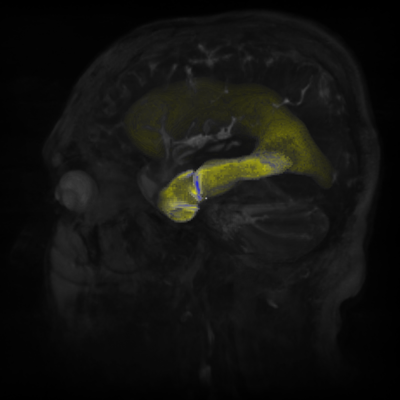

Figure 41.1 depicts a human torso and part of a skull (OpacityMapRenderStyle) blended with a blue/yellow tone-mapped volume of the internal organs. The image shows how BlendedVolumeStyle allows two different volumes to be combined, each with its own render style.

Figure 41.1 — Torso in BlendedVolumeStyle